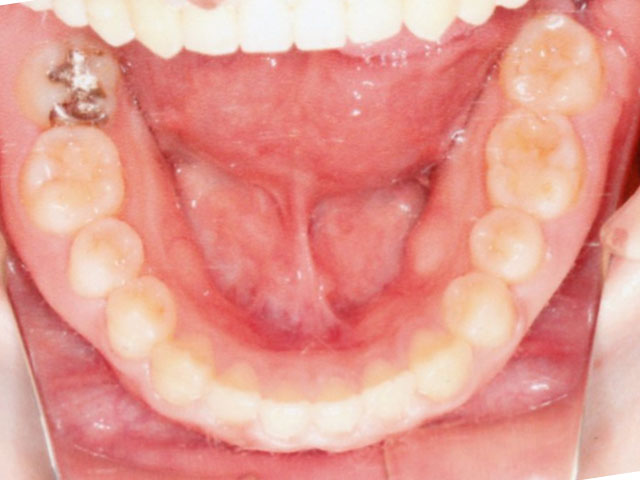

症例02【空隙歯列】

16歳9か月(男子)

上下の顎の成長・発育のバランスには問題はなく、骨格的な不調和は認められませんでした。

ただし、歯の大きさが平均よりもやや小さいことに加え、舌で前歯を押し出す癖(舌突出癖)がみられ、これが前歯の位置に影響している状態でした。

そのため、治療計画は非抜歯とし、スタンダードエッジワイズ法による矯正治療を選択。

治療期間は1年11か月で、その後は保定へ移行。

- 空隙歯列